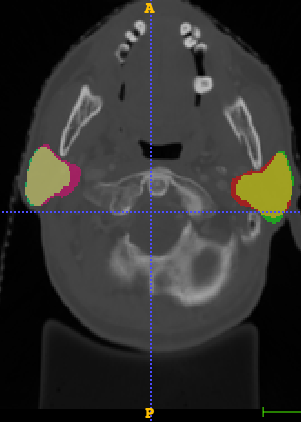

In Chapter 6, we propose an end-to-end, atlas-free 3D convolutional deep learning framework for fast and fully automated whole-volume HaN anatomy segmentation [115]. Our deep learning model, called AnatomyNet, segments OARs from head and neck CT images in an end-to-end fashion, receiving whole-volume HaN CT images as input and generating masks of all OARs of interest in one shot. AnatomyNet is built upon the popular 3D U-net architecture, but extends it in three important ways: 1) a new encoding scheme to allow auto-segmentation on whole-volume CT images instead of local patches or subsets of slices, 2) incorporating 3D squeeze-and-excitation residual blocks in encoding layers for better feature representation, and 3) a new loss function combining Dice scores and focal loss to facilitate the training of the neural model. These features are designed to address two main challenges in deep-learning-based HaN segmentation: a) segmenting small anatomies (i.e., optic chiasm and optic nerves) occupying only a few slices, and b) training with inconsistent data annotations with missing ground truth for some anatomical structures. We collect 261 HaN CT images to train AnatomyNet, and use MICCAI Head and Neck Auto Segmentation Challenge 2015 as a benchmark dataset to evaluate the performance of AnatomyNet. The objective is to segment nine anatomies: brain stem, chiasm, mandible, optic nerve left, optic nerve right, parotid gland left, parotid gland right, submandibular gland left, and submandibular gland right. Compared to previous state-of-the-art results from the MICCAI 2015 competition, AnatomyNet increases Dice similarity coefficient by 3.3% on average. AnatomyNet takes about 0.12 seconds to fully segment a head and neck CT image of dimension , significantly faster than previous methods. In addition, the model is able to process whole-volume CT images and delineate all OARs in one pass, requiring little pre- or post-processing. We demonstrate that our proposed model can improve segmentation accuracy and simplify the auto-segmentation pipeline. These contributions are released as an open-source software package called AnatomyNet, which is publicly available555https://github.com/wentaozhu/AnatomyNet-for-anatomical-segmentation. Portions of this chapter were published as part of [115].